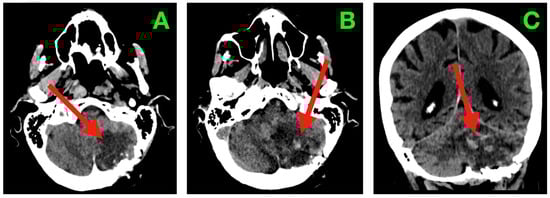

Neuroimaging at this time (Figure 3) demonstrated structural correlates to favorable clinical recovery. The post-operative cavity within the left neocerebellar hemisphere was well shown with axial CT imaging (Figure 3A), with complete collapse of volume of residuum from the previous surgery, with evidence of a mass effect on the fourth ventricle from before the previous surgery. The cavity was well delineated with smooth gliotic cavity walls, with the absence of irregular nodularity implying evidence of residuum. The attenuation of the parenchyma surrounding the cavity appeared normal. The cavity measured superiorly from the superior folial tiers to above the foramen magnum and spared the vermis and dentate nucleus medially while confirming that the undersurface of the tentorium maintained its anatomical relationship without upward displacement. The basal cisterns remained patent, including the prepontine and cerebellopontine cisterns. No signs of hydrocephalus, transependymal CSF seepage, or hemorrhagic sequelae were observed.

Figure 3. Two-week post-operative CT scan. (A) Axial non-contrast CT through the posterior fossa demonstrates a sharply delineated post-operative resection cavity within the left neocerebellar hemisphere (arrow), corresponding to the site of tumor excision. The cavity margins are smooth and gliotic, without irregularity or nodularity to suggest residual tumor. The surrounding cerebellar parenchyma exhibits homogeneous attenuation with no focal hypoattenuation suggestive of ischemia and no hyperdense collections indicating hemorrhage. The ipsilateral transverse and sigmoid sinuses remain patent, and the fourth ventricle has returned to midline with restored anteroposterior diameter. Perifocal edema present in the immediate post-operative period has resolved, as evidenced by normalization of parenchymal density and the absence of sulcal effacement. The basal cisterns are widely patent, including the prepontine, cerebellopontine, and cerebellomedullary cisterns, confirming unobstructed CSF pathways in the posterior fossa. (B) Coronal CT reconstruction depicts the vertical profile of the resection cavity (arrow), extending from the superior folial tiers of the cerebellar hemisphere to just above the foramen magnum, while preserving the integrity of the vermis and sparing the dentate nucleus medially. The tentorial undersurface maintains its normal concavity, with no evidence of superior displacement or distortion. The cisterna magna appears well-formed and free of mass effect. No pneumocephalus, extra-axial collections, or pseudomeningocele are present. These findings are consistent with a complete macroscopic resection, preservation of critical cerebellar and brainstem structures, and a complication-free post-operative evolution at this time point.

The post-operative course within this time interval was uneventful with no surgical site infection, CSF leak, pseudomeningocele, or compromise to wound healing. The functional evaluation was consistent with clinical improvement with the modified Rankin Scale improving from 3 on admission to 1 at this time point. This indicated a highly favorable neurological recovery, with only negligible residual findings detectable based on high-demand coordination testing.